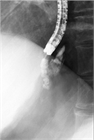

1. 食道・胃静脈瘤は慢性肝疾患などによる門脈圧亢進症に伴って代償的に形成される側副血行路の1つである。

1. 胃静脈瘤:内視鏡的塞栓術(Histoacrylによる)、バルーン閉塞下逆行性経静脈的塞栓術(balloon-occluded retrograde transvenous obliteration:B-RTO)を行う。